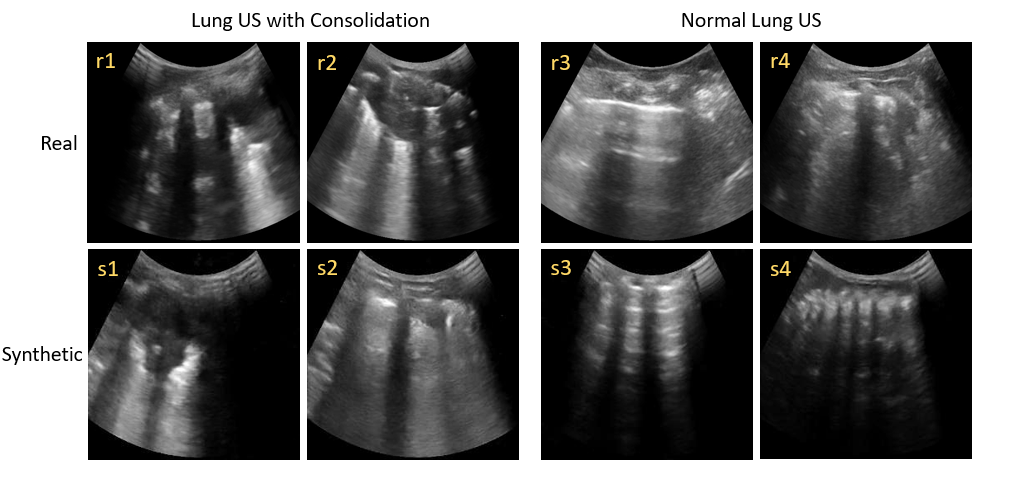

Refer to caption

Figure 3: Examples of real and synthetic images.

Lung ultrasound images largely consist of artifacts generated by acoustic impedance mismatches between lung tissue, fluid, and air. To the trained eye, these artifacts convey information about lung pathologies such as consolidation, which manifests as sub-pleural hyper- and hypo-echoic splotches caused by inflammatory alveolar fluid buildup. See Figure 1. We observe that the synthetic images also display such features and artifacts and preserve the architecture of lung ultrasound images. Figure 3 shows examples of synthetic and real, consolidated and normal, lung ultrasound images. Prominent features of lung ultrasound include the “bat sign” [2] and “rib shadows”, caused by the pleural line and the impenetrability of ribs to ultrasound. These can be observed in the real and synthetic lung images (r1–r4, s1–s4). Pleural lines, A-lines (multiple-echo artifacts of the pleural line) are also present and qualitatively similar in synthetic images (r3, s3). The “shadows” on the left and right sides of images (r1, r2, r4, s1–s4) are caused by poor acoustic contact between the edges of the curvilinear transducer and the child’s body, which is another realistic element of the the synthetic images. Other features of lung ultrasound also appear in synthetic images, such as “hepatization”, caused by excessive fluid accumulation, as seen in (s1, s2). Additional synthetic examples are provided in the supplement.